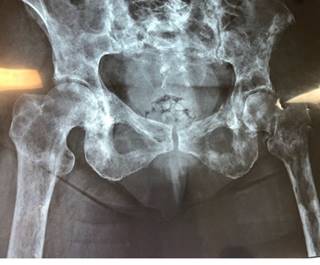

La tomografía axial computarizada evidenció una lesión ósea en dicho nivel asociada a múltiples lesiones de aspecto «en panal de abejas» diseminadas en la economía vertebral (Figura 5).

En la región sacra se evidenció una lesión tumoral hiperintensa de bordes regulares, redonda, la cual se alojaba en el cuerpo vertebral de S2 (Figura 6), así como la presencia de múltiples cuerpos vertebrales torácicos y lumbares afectados por lesiones de características similares. Finalmente, tres días después de su reingreso, el paciente fallece a causa de un tromboembolismo pulmonar fulminante.